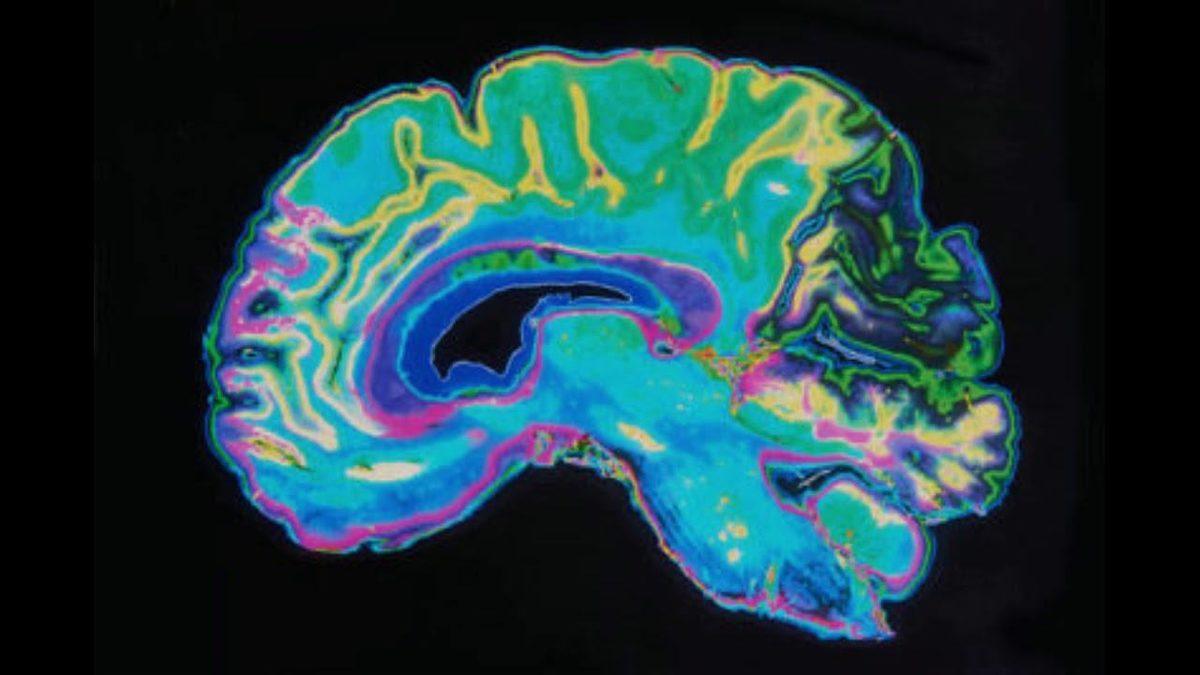

İnsan beyni sırlarla dolu ve bilim insanları bu sırrı çözmek için ellerinden geleni yapıyorlar. Beynin sırlarından biri de gri madde ve bu maddenin oluşumunu anlamayı amaçlayan araştırmacılar, laboratuvarda mini bir beyin üretmişti.

Yetişkin kök hücrelerinden yapılan bu ’beyinsel organımsı’lar yaklaşık 10 yıldır kullanılmasına rağmen gerçek anlamda bir nöral ağ ilk defa kuruldu. Kaliforniya San Diego Üniversitesi’nden Alysson Muotri, yaptığı açıklamada beş yıl önce kendisine yapay beyinde harekteler gözlemleyebilecekleri spesifik bir yapı olup olmayacağı sorulsa, olmayacağını söyleyeceğini belirtti. Moutri ve ekibi tarafından yayımlanan makalede bu atılımı mümkün kılan 2 yapı öne çıkarıldı. Bunlardan ilki kök hücrelerinin gelişimi için daha iyi prosedürlerin olması, diğeri de nöronlara uyum sağlama izinlerinin verilmesi oldu.

Muotri, insan nörogelişiminin ilk aşamalarının genetik kodlarımızda kayıtlı olduğunu söylüyor. İlk olarak çok ilkel ve zayıf beyin dalgaları görülen organımsılar büyüdükçe daha farklı frekanslarda sinyaller de yaymaya başladı.

Erken doğan bebeklerin beyin aktiviteleri ile organımsıdaki gelişimi inceleyen bilim insanları, yapının doğal bir beyinle aynı şekilde geliştiğini gözlemledi.